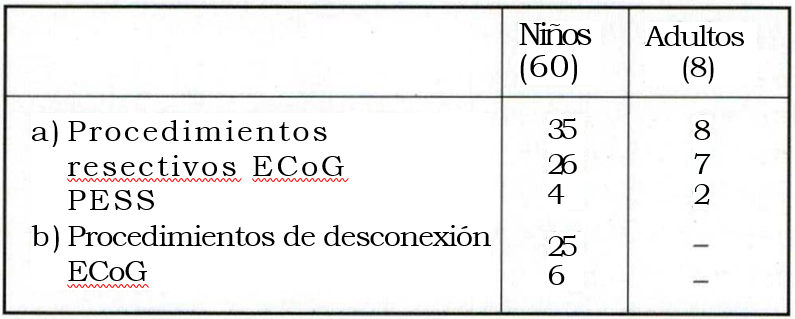

La tabla 7 da cuenta de los procedimientos quirúrgicos realizados y la tabla 8 resume los estudios neurofisiológicos intraoperatorios en los diversos procedimientos

Tabla 7. Procedimientos quirúrgicos

En cuanto a la evaluación intraoperatoria, la ECoG tuvo un rol importante en los procedimientos resectivos (26/35) y en menor medida en los de desconexión. En este subgrupo fue útil para las desconexiones lobares (6/25). No se utilizó en las hemisferectomías, hemisferotomías ni en las callosotomías.10. Los PESS se usaron en las epilepsias del área central (4/35) para determinar con certeza las áreas sensoriales y motoras primarias del cerebro.